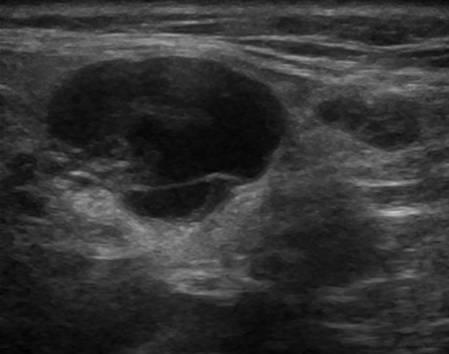

U tuyến nước bọt

» Thông tin: Nam giới – 71 tuổi.

» Lâm sàng: Khối vùng mang tai.

# U lympho tuyến nang (U Warthin) tuyến nước bọt mang tai.